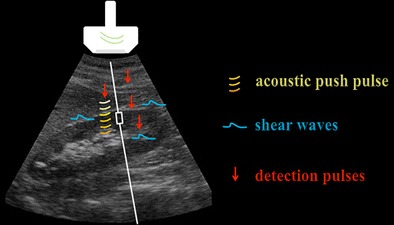

In the ARFI technique, the shear waves exciting the target tissue are generated inside a fixed-size (1 x 0.5 cm) region of interest (ROI), placed at the choice of the operator on a conventional gray-scale ultrasound (US) image. In brief, focused, short-duration acoustic push pulses travelling along the main US beam [1] induce within tissues shear stresses, with modalities and intensities depending upon tissue attenuation (mainly due to absorption), acoustic frequency, and intensity of the acoustic beam [2]. In turn, the shear stresses give rise to shear waves that propagate, perpendicular to the main US beam, away from the original region of excitation (Fig. 1). In a theoretical, perfectly homogeneous and isotropic target, the speed of propagation of the shear waves is directly proportional to the density and to the shear modulus of the tissue [1], the latter being related to its elasticity. Therefore, if density does not vary, softer tissues exposed to a given radiation force move farther than stiffer tissues, and, having a lower shear modulus, take longer to reach their peak displacement (on the order of tens of microns), and recover more slowly [3].

Fig. 1.

Schematic representation of the ARFI technique. On a conventional gray-scale US image (oblique scan including the right kidney and the lowest portion of the right lobe of the liver), acoustic push pulses (curved lines) are generated together with the main US beam. From the push pulses originate shear waves (dashed horizontal lines) propagating perpendicular to the main US beam, which are sampled by tracking beams (arrows) parallel to the main beam. The actual distance covered by the shear waves before their attenuation is limited: the data concerning tissue response can only be achieved within a small ROI (rectangular box along the straight vertical line)

Together with the push pulses, low-intensity tracking US beams are continuously emitted parallel to the main beam in order to monitor the tissue displacement. The tracking beams intercept the shear wave front at several predetermined locations and time intervals, which allows a series of data concerning the tissue response to be obtained, such as the time-to-peak displacement and the recovery time (Fig. 1). From these data, mainly through time-of-flight algorithms, quantitative estimates of the speed of propagation of the shear waves, and then of the tissue stiffness, are obtained [1, 4]. Such information can be displayed by ARFI systems as either a map reflecting spatial differences in tissue stiffness, or—more commonly—quantitatively: in most cases, the tissue elasticity is then expressed as shear wave velocity (SWV), usually measured in meters per second (m/s).